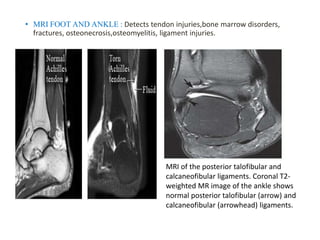

• MRI FOOT AND ANKLE : Detects tendon injuries,bone marrow disorders,

fractures, osteonecrosis,osteomyelitis, ligament injuries.

MRI of the posterior talofibular and

calcaneofibular ligaments. Coronal T2-

weighted MR image of the ankle shows

normal posterior talofibular (arrow) and

calcaneofibular (arrowhead) ligaments.